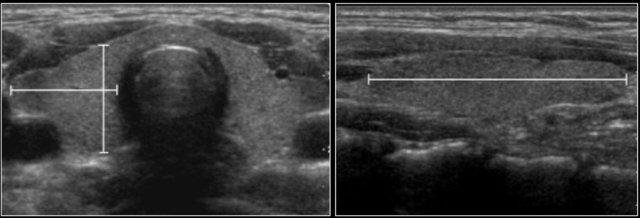

Đo thể tích tử cung và buồng trứng bằng siêu âm được thực hiện trên 178 bé gái khỏe mạnh.

Thể tích buồng trứng được tính theo công thức:

- Chiều dài x Chiều rộng x Chiều cao x 0,523.

Thể tích tử cung được tính theo công thức hình elipsoid:

Chiều dài × Chiều rộng × Chiều cao × 0,523